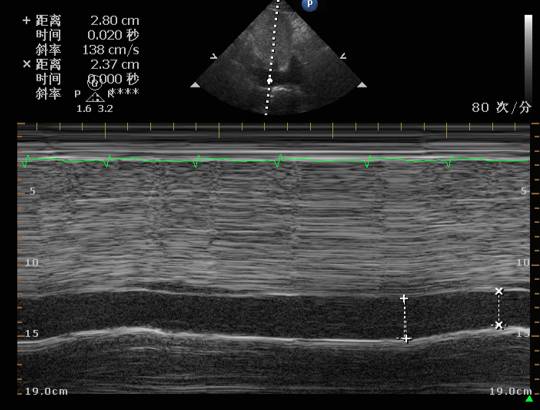

心脏彩超

右:左=1:1

IVC>2.5cm

EF:0.35

♥床边心超提示:心率增快时左心收缩力明显减弱,伴充盈压高,予以艾司洛尔(0.05mg/kg/min)控制心室率后心率降至55左右,血压明显改善,102/70mmHg,复查心超左心收缩舒张功能均改善。